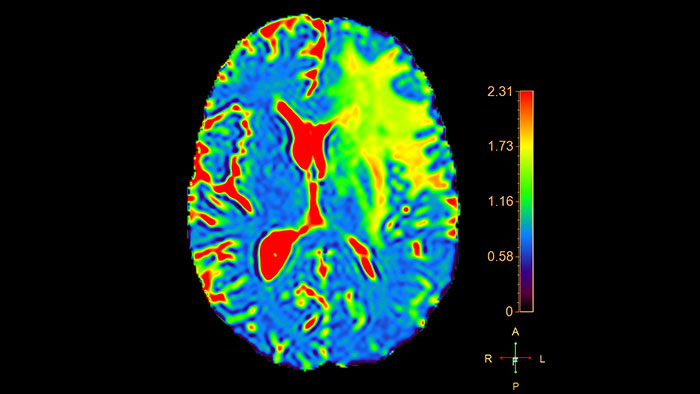

Reviewing brain tissue perfusion viability

Provides physicians with supporting information for the evaluation of stroke, or assessment and follow-up of brain tumors. The application supports the analysis of T2* Perfusion studies to generate parametric data including TTP, MTT or Tmax.